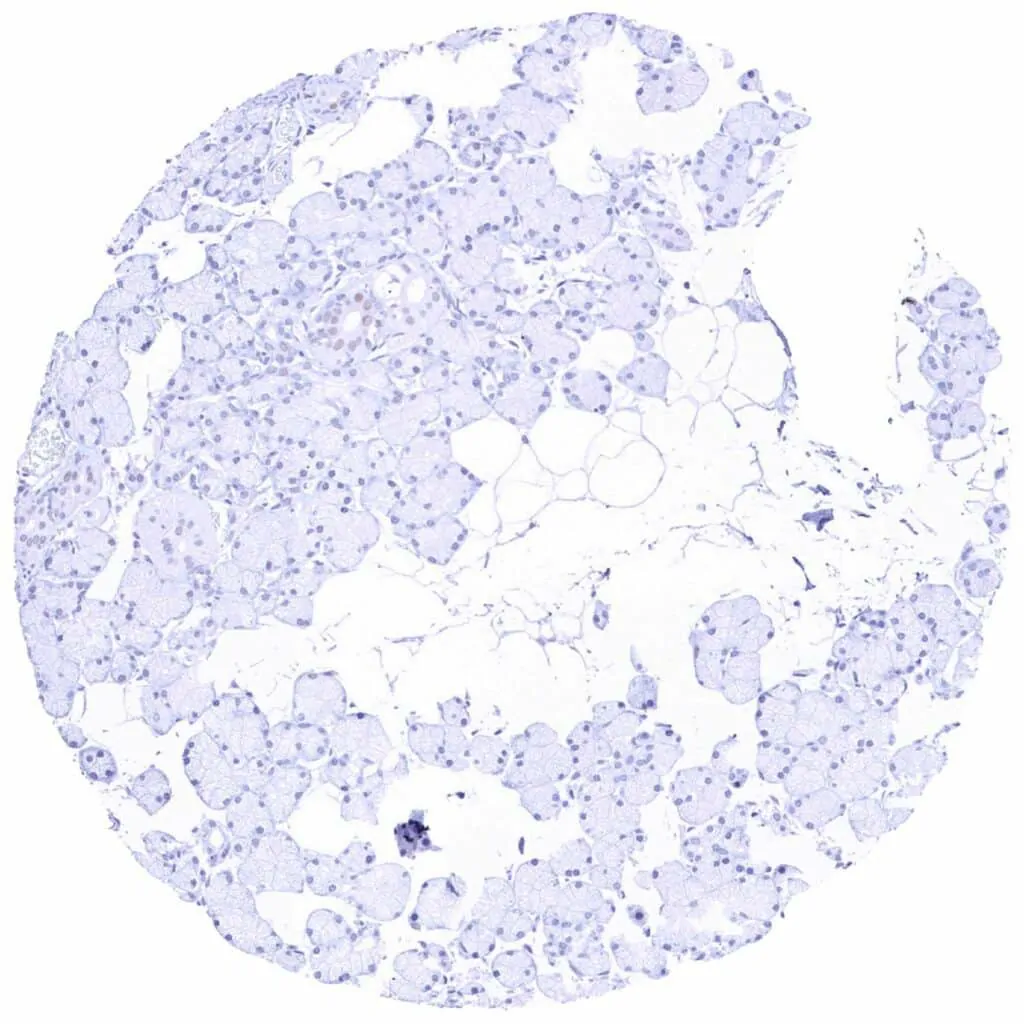

Pancreas